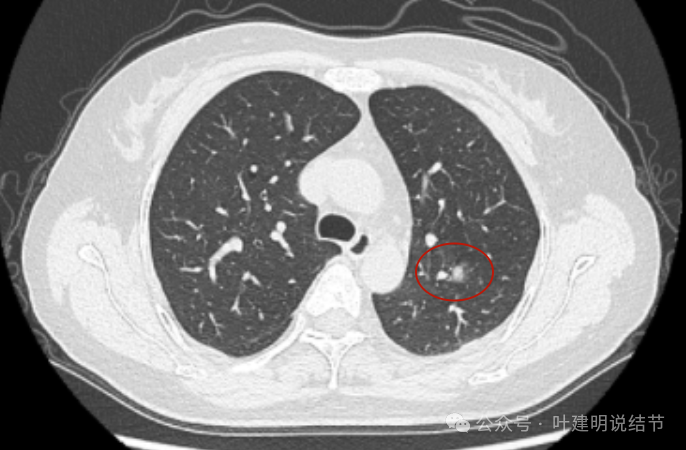

病灶出现,边缘区表面不是很光滑,似有少许磨玻璃成分以及边缘略显毛糙。

表面不是太光滑,中间的密度略显低。

血管贴得近,但没有牵拉或分支进入病灶,整体表面较为光滑。

与血管关系近,结节有膨胀感。

此层看与血管紧贴,没有间隙。局部有轻凹陷。

病灶明显感觉较为膨胀。

似见血管征,表面欠平滑,倾向浅分叶的样子。

边缘区密度不是太致密,有点像磨玻璃偏实的样子。

边缘区域混合密度的表现。